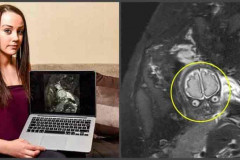

Տեսնելով պտղի սոնոգրաֆիայի նկարները՝ ծնողները շոկի մեջ ընկան. միայն տեսեք, թե ին...